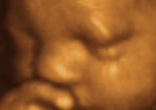

America's Shame: Using Ultrasound Technology for Saving Babies and Killing Babies in the Womb Watch

Tammy had been told that her little girl had a tumor on her mouth which, left alone, would grow and may lead to her death even before ... continue reading